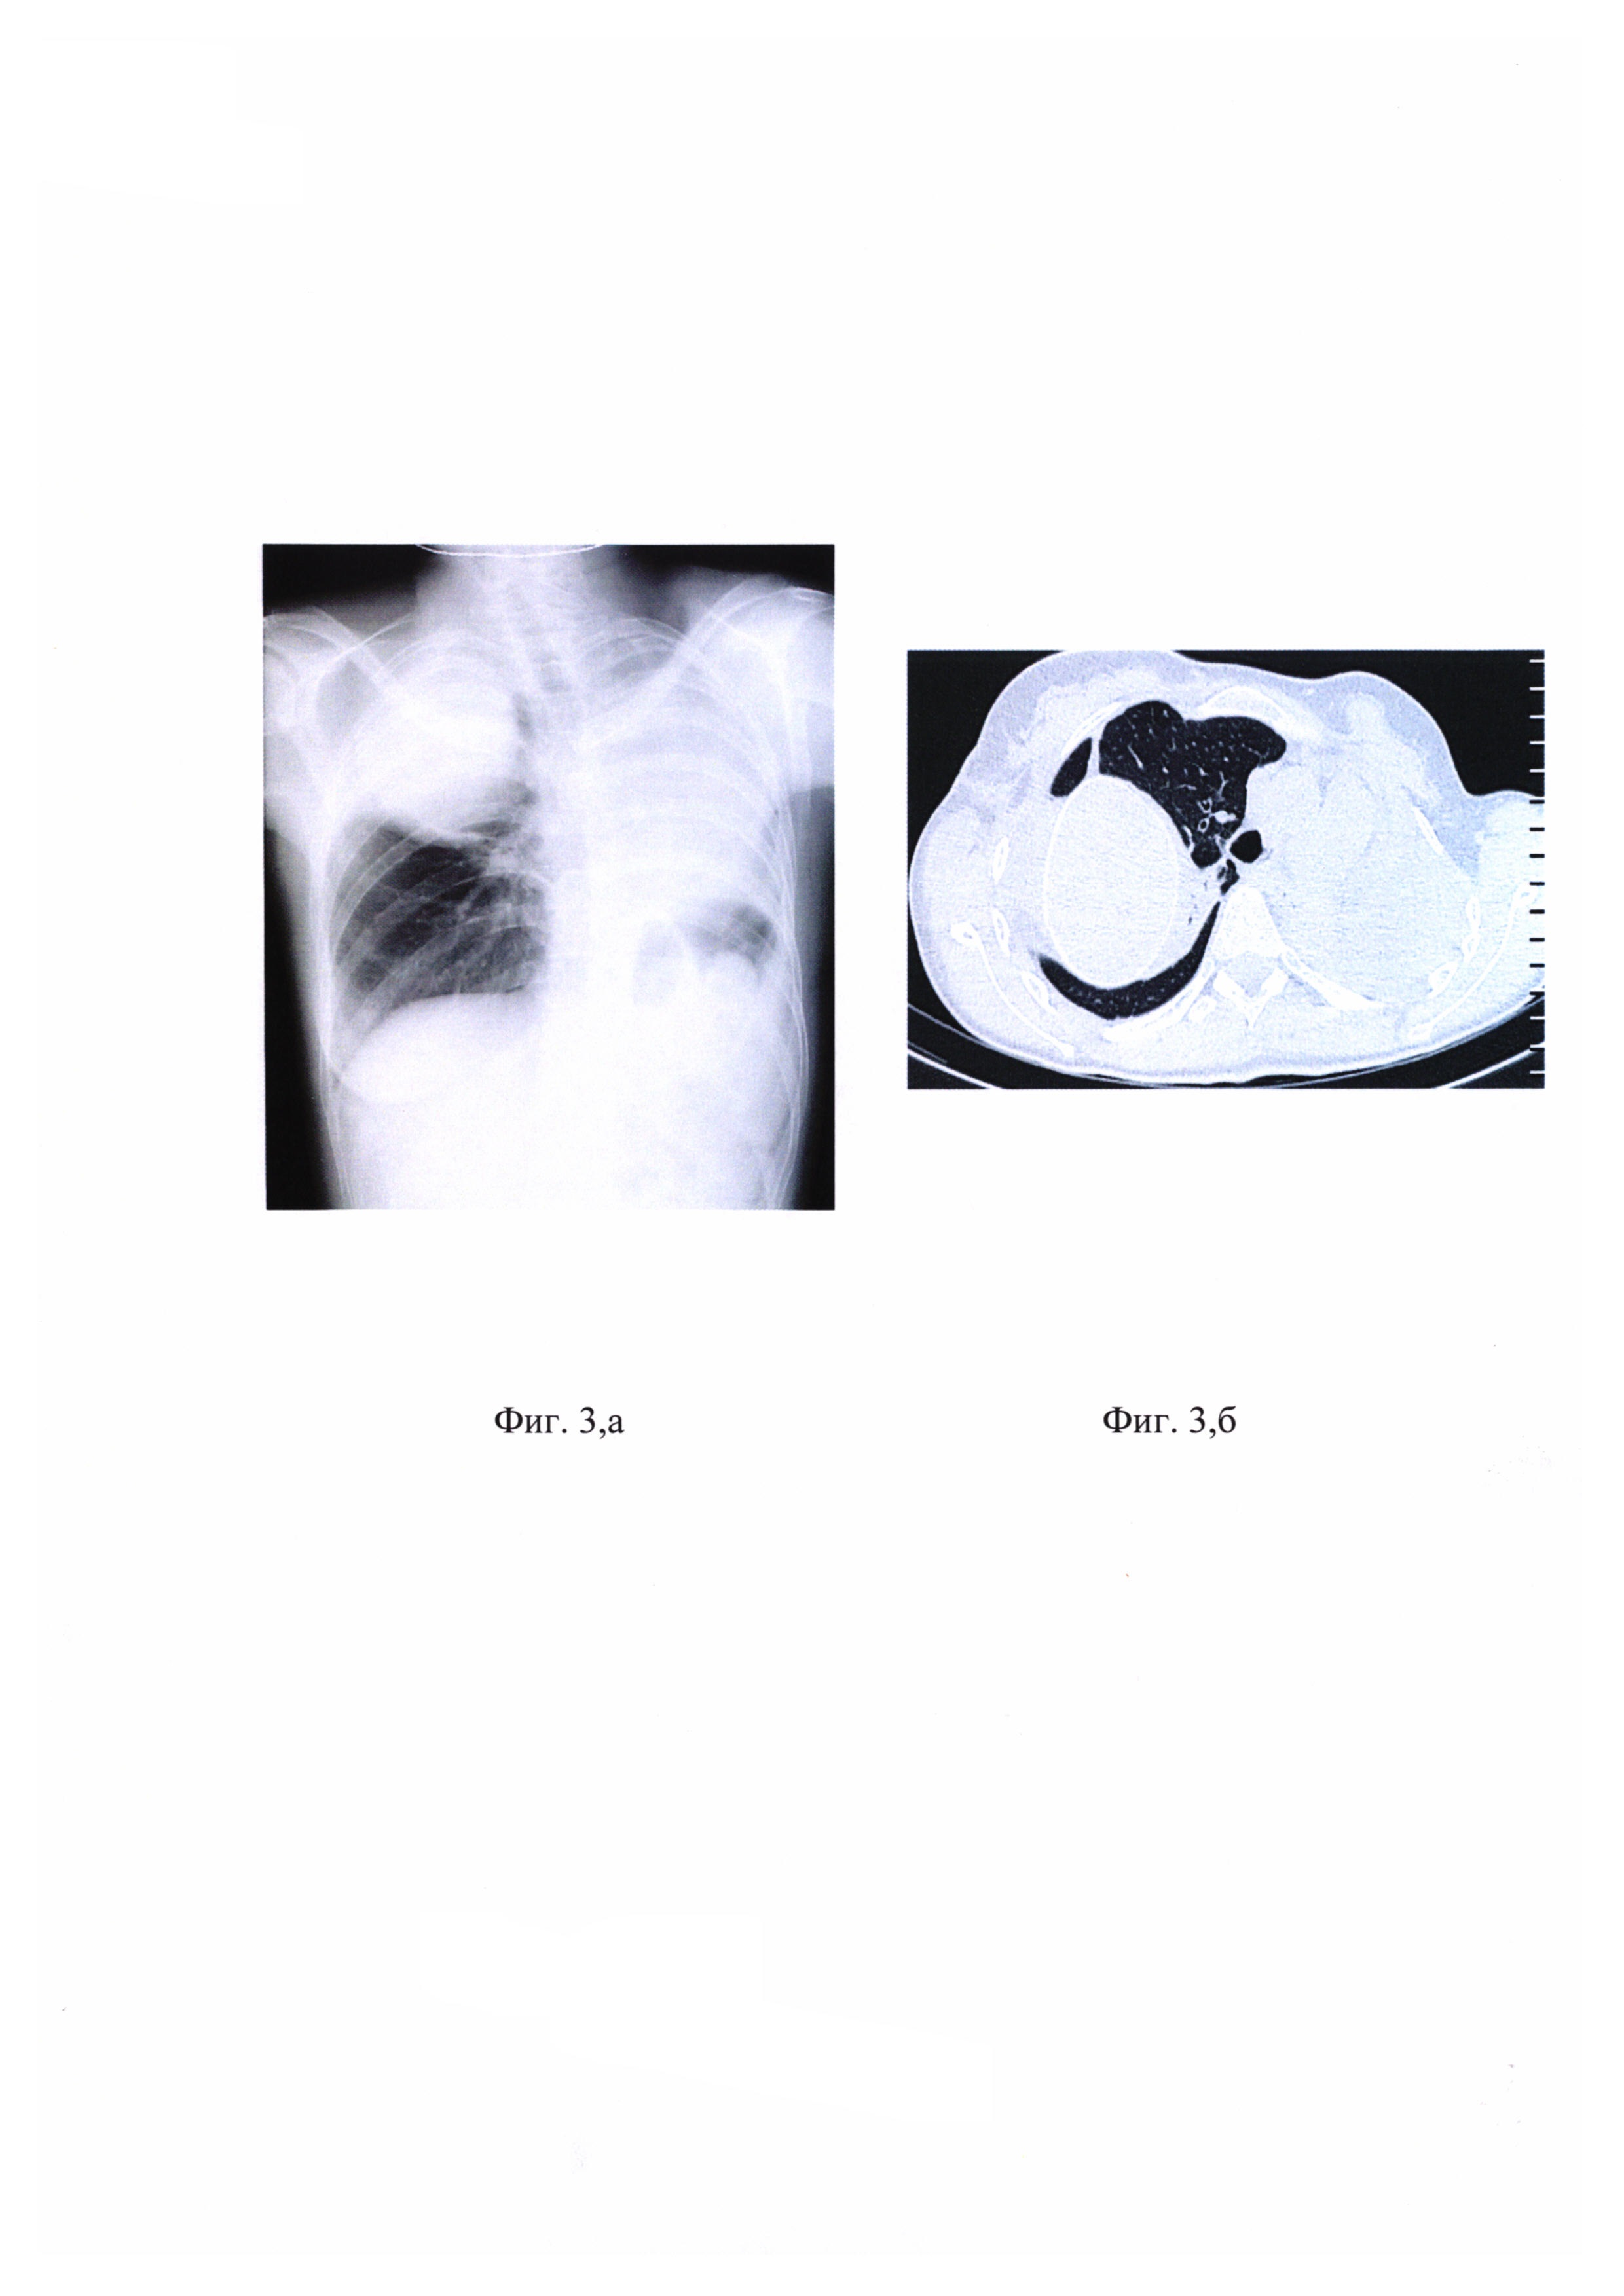

на фиг 1, а - КТ органов грудной клетки, разрушенное левое легкое;

на фиг. 1, б - КТ органов грудной клетки, в верхней доле - крупная каверна, множественные полиморфные очаги, крупные - с признаками распада;

на фиг. 2 - КТ органов грудной клетки в динамике, сохраняется каверна в правом легком, частичное рассасывание очаговых и инфильтративных изменений;

КТ органов грудной клетки представлено на фиг. 1, а - разрушенное левое легкое, на фиг. 1, б - крупная каверна в верхней доле. Имеются множественные полиморфные очаги, крупные с признаками распада.

Состояние больной осложнилось эпизодами рецидивирующего кровохарканья. При фибробронхоскопии выявлено поступление крови из верхнедолевого бронха слева. На консилиуме было решено провести больной двухэтапное лечение с применением плевропневмонэктомии на первом этапе по срочным показаниям и экстраплеврального пневмолиза с пломбировкой силиконом на втором этапе. На 1 этапе больной выполнена операция плевропневмонэктомия слева. Гистологическое исследование: фиброзно-кавернозный туберкулез с участками отсева, выраженная активность туберкулезного процесса Послеоперационный период проходил без осложнений. На фиг. 2 - КТ органов грудной клетки в динамике. Сохраняется каверна в правом легком. Частичное рассасывание очаговых и инфильтративных изменений. Через 2,5 месяца больной выполнен второй этап хирургического лечения: экстраплевральный пневмолиз справа с установкой силиконовой пломбы.